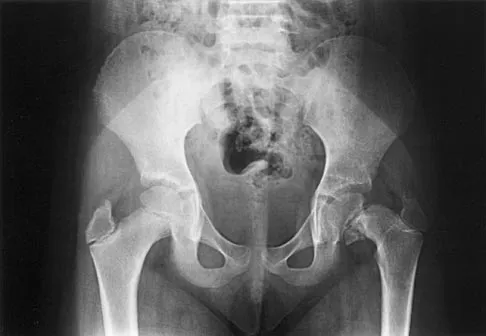

The mother of a 26-month-old boy reports that he has been unwilling to bear weight on his left lower extremity since he awoke this morning. She denies any history of trauma. He has a temperature of 99.4 degrees F (37.4 degrees C), and examination reveals that abduction of the left hip is limited to 30 degrees. Laboratory studies show a WBC of 11,000/mm3 and an erythrocyte sedimentation rate of 22 mm/h. A radiograph of the pelvis is shown in Figure 13. Management should consist of

Explanation

The most likely diagnosis is transient synovitis. Initial management should consist of bed rest and serial observation to rule out atypical septic arthritis of the hip. In an unreliable family situation, hospitalization for bed rest and observation may be indicated. Other disorders such as proximal femoral osteomyelitis, leukemia, juvenile rheumatoid arthritis, pelvic osteomyelitis, diskitis, and arthralgia secondary to other inflammatory disorders should be considered. However, these disorders are unlikely because of the paucity of abnormal clinical signs exhibited by the patient. On the other hand, transient synovitis of the hip in children is a diagnosis of exclusion; other possibilities should be explored if the patient's symptoms do not follow a typical course and resolve in 4 to 21 days.